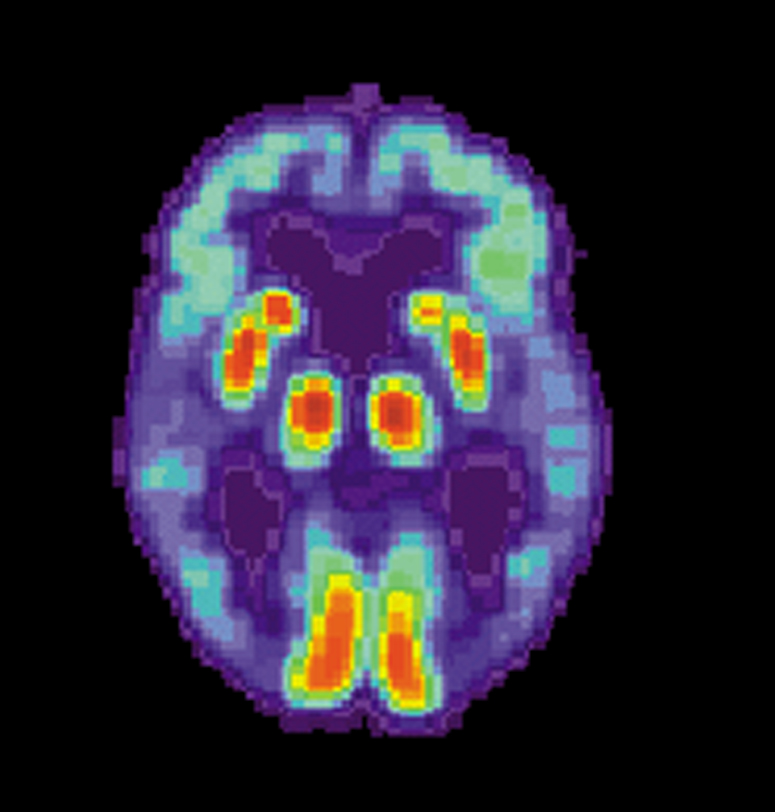

The specific causes of Alzheimer’s are unknown, but the disease is characterized by changes in the brain, including the presence of amyloid beta plaques and neurofibrillary tangles. These changes lead to the loss of neurons and their connections, resulting in cognitive decline.

During the trial, patients receiving Leqembi demonstrated a significant reduction of amyloid beta, which was both dose and time dependent. Notably, patients who received the approved dose of lecanemab, 10 milligrams/kilogram every two weeks, exhibited a statistically significant reduction of brain amyloid from baseline to 79 weeks.